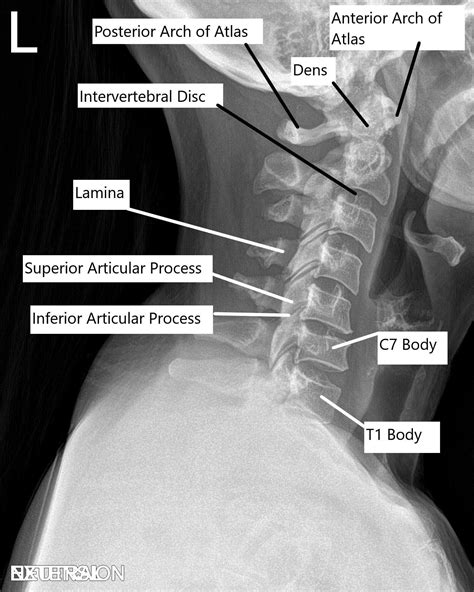

• Medical Evaluation: Your surgeon will conduct a thorough medical evaluation, including a physical examination, imaging tests (such as X-rays, MRI, or CT scans), and possibly neurological tests.

The Anterior Cervical Fusion procedure involves several critical steps. Here is a detailed overview of what to expect during the surgery:

• anterior cervical fusion xray